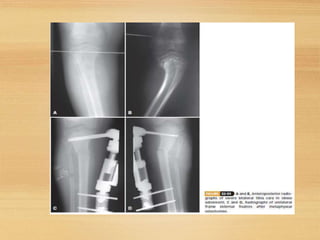

• Tibial osteotomy. In this procedure, theshinbone

is cut just below the knee and reshaped to

correct the alignment.

• After surgery, acast may be applied to protect

the bone while it heals.

METAPHYSEAL OSTEOTOMY

FOR TIBIA VARA